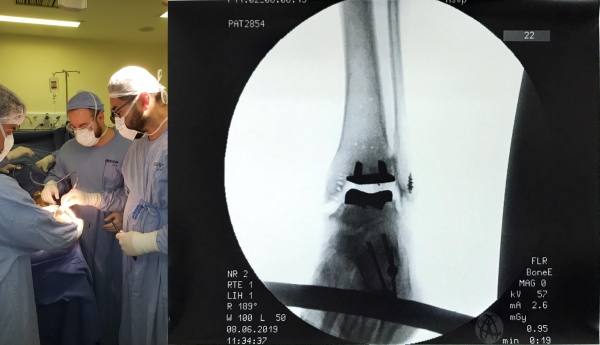

Neste mês de junho, o ortopedista e traumatologista Cristhopher Lucca Stoffel, auxiliado pelos médicos Dr. Gilberto Nascimento e o Dr. Everton de Lima realizou a primeira artroplastia total de tornozelo do Rio Grande do Sul, no Hospital São Vicente de Paulo (HSVP) de Passo Fundo.

“ O grande benefício da técnica é o alívio da dor, mantendo a mobilidade da articulação, preservando dessa maneira a integridade das articulações adjacentes”, explica Dr. Stoffel, exemplificando que, a “outra cirurgia que temos para tratar artrose do tornozelo é a artrodese da articulação, que consiste na fusão da mesma, causando perda da mobilidade, e artrose (desgaste) das articulações adjacentes com o passar dos anos”.

O procedimento que surge como uma esperança para os pacientes com artrose ou desgaste da articulação do tornozelo, tem como principal diferencial é a preservação da mobilidade da articulação. A recuperação para os pacientes “que realizam a prótese ao invés da artrodese é mais breve, pois voltam a caminhar com apoio do peso mais rapidamente que os pacientes submetidos à artrodese”. A cirurgia é indicada pelo Ortopedista e traumatologista após exames e avaliação.